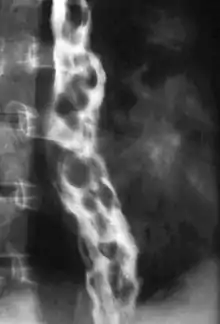

| Gastroscopy image of esophageal varices with prominent cherry-red spots | |